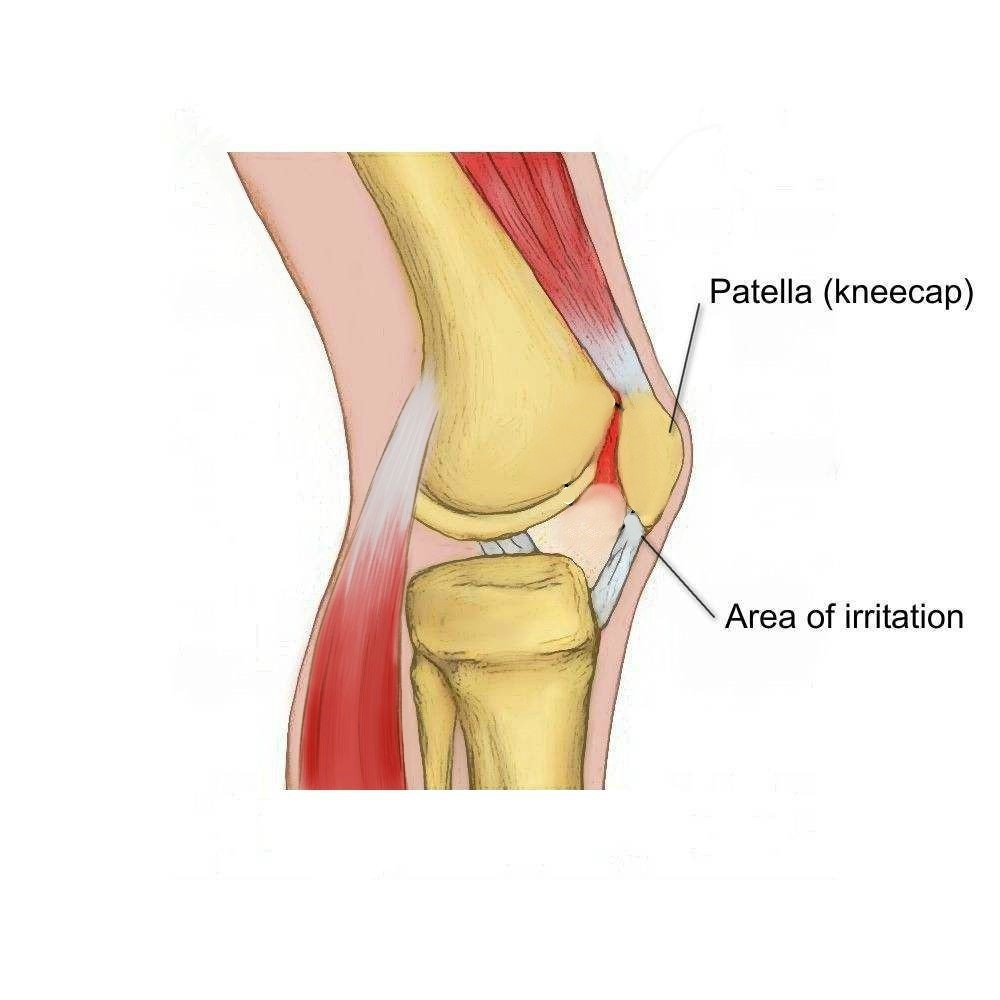

Анатомия коленного сустава: изучение анзерита и его влияния